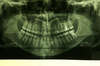

Les radios avant le traitement